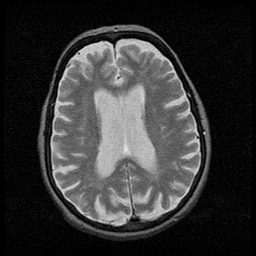

Huntington's Chorea, MR -- Slice #12

[Home][Help][Clinical] Slice 12